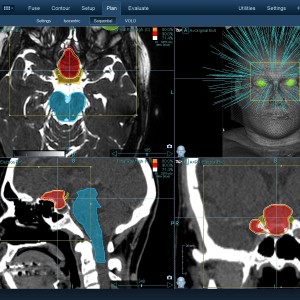

Στις παρακάτω φωτογραφίες θα δείτε παραδείγματα πλάνων θεραπείας καρκινικών όγκων με CyberKnife. Παρατηρήστε πόσο κοντά στους υγιείς ιστούς βρίσκονται οι καρκινικοί όγκοι που χρειάζεται να ακτινοβοληθούν. Μόνο με το CyberKnife και το προσωπικό πλάνο θεραπείας, μπορούν να ακτινοβοληθούν οι όγκοι χωρίς να πληγούν οι παρακείμενοι υγιείς ιστοί.

Μόνο με το CyberKnife και την κατάλληλη σχεδίαση της θεραπείας από έμπειρο νευροχειρουργό, μπορεί να ακτινοβοληθούν οι όγκοι χωρίς να επηρεαστούν από την ακτινοβολία οι υγιείς ιστοί. Αυτό εξασφαλίζει τη μέγιστη δυνατή απόδοση της ακτινοχειρουργικής θεραπείας των όγκων.

Ο νευροχειρουργός Λέκας Λεωνίδας έχει τη μεγαλύτερη εμπειρία στην Ελλάδα στο σχεδιασμό θεραπειών στερεοτακτικής ακτινοχειρουργικής όγκων του εγκεφάλου και του νευρικού συστήματος σε CyberKnife. Ο σχεδιασμός του πλάνου θεραπείας προϋποθέτει άριστη γνώση της ανατομίας και της απεικόνισης του κεντρικού νευρικού συστήματος έτσι ώστε να επιτευχθεί το βέλτιστο θεραπευτικό αποτέλεσμα με τη μέγιστη δυνατή προστασία των ευαίσθητων δομών.

Με κόκκινο χρώμα περιγράφεται η περιοχή του όγκου.

Με μπλε, κίτρινο και πράσινο χρώμα περιγράφονται οι υγιείς ιστοί που δεν πρέπει να ακτινοβοληθούν.

Παρατηρήστε πόσο κοντά βρίσκεται ο όγκος με τους υγιείς ιστούς.

Παρατηρήστε τις πάρα πολλές δέσμες του CynerKnife που ακτινοβολούν τους όγκους από διαφορετικές γωνίες ώστε να μην προσβληθούν από την ακτινοβολία οι υγιείς ιστούς.